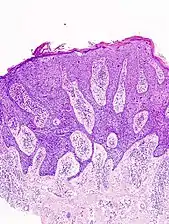

In situ disease

Bowen's disease is essentially equivalent to and used interchangeably with cSCC in situ, when not having invaded through the basement membrane.[12] Depending on source, it is classified as precancerous[13] or cSCC in situ (technically cancerous but non-invasive).[47][48] In cSCC in situ (Bowen's disease), atypical squamous cells proliferate through the whole thickness of the epidermis.[12] The entire tumor is confined to the epidermis and does not invade into the dermis.[12] The cells are often highly atypical under the microscope, and may in fact look more unusual than the cells of some invasive squamous-cell carcinomas.[12]

In invasive cSCC, tumor cells infiltrate through the basement membrane. The infiltrate can be somewhat difficult to detect in the early stages of invasion: however, additional indicators such as full thickness epidermal atypia and the involvement of hair follicles can be used to facilitate the diagnosis. Later stages of invasion are characterized by the formation of nests of atypical tumor cells in the dermis, often with a corresponding inflammatory infiltrate.[12]